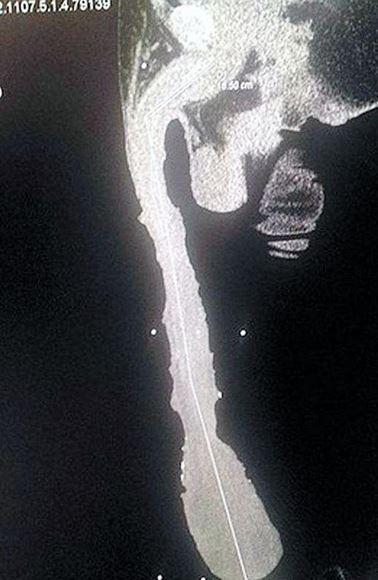

52 yaşındaki Cabrera'nın 48.2 santimetre boyutundaki penisinin çapı ise 25 santimetre.

Girdiği her ortamda insanların ondan kaçındığını söyleyen Cabrera, 2011 yılından beri kardeşinin kendisine verdiği bir odada yaşamını sürdürüyor. Guiness Rekorlar Kitabı'nda böyle bir kategori henüz oluşturulmadığı için resmi olarak en uzun penisli seçilmesi biraz zaman alacak olan Cabrera, bunun için bir röntgen de çektirdi.